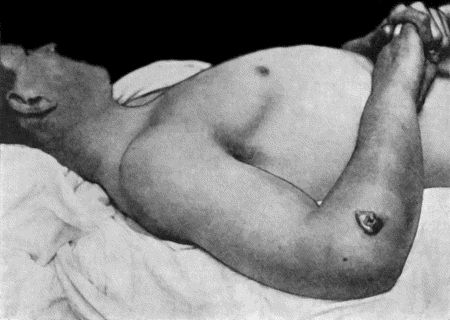

| 21. | Embolic Gangrene of Hand and Arm | 92 |